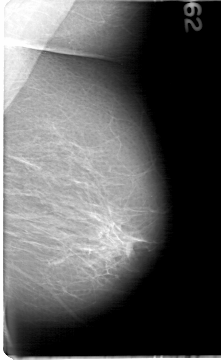

D_4081_1.LEFT_MLO

LEFT_MLO LINES 5386 PIXELS_PER_LINE 3301 BITS_PER_PIXEL 12 RESOLUTION 43.5 NON_OVERLAY

D_4081_1.LEFT_CC

LEFT_CC LINES 5386 PIXELS_PER_LINE 3136 BITS_PER_PIXEL 12 RESOLUTION 43.5 NON_OVERLAY